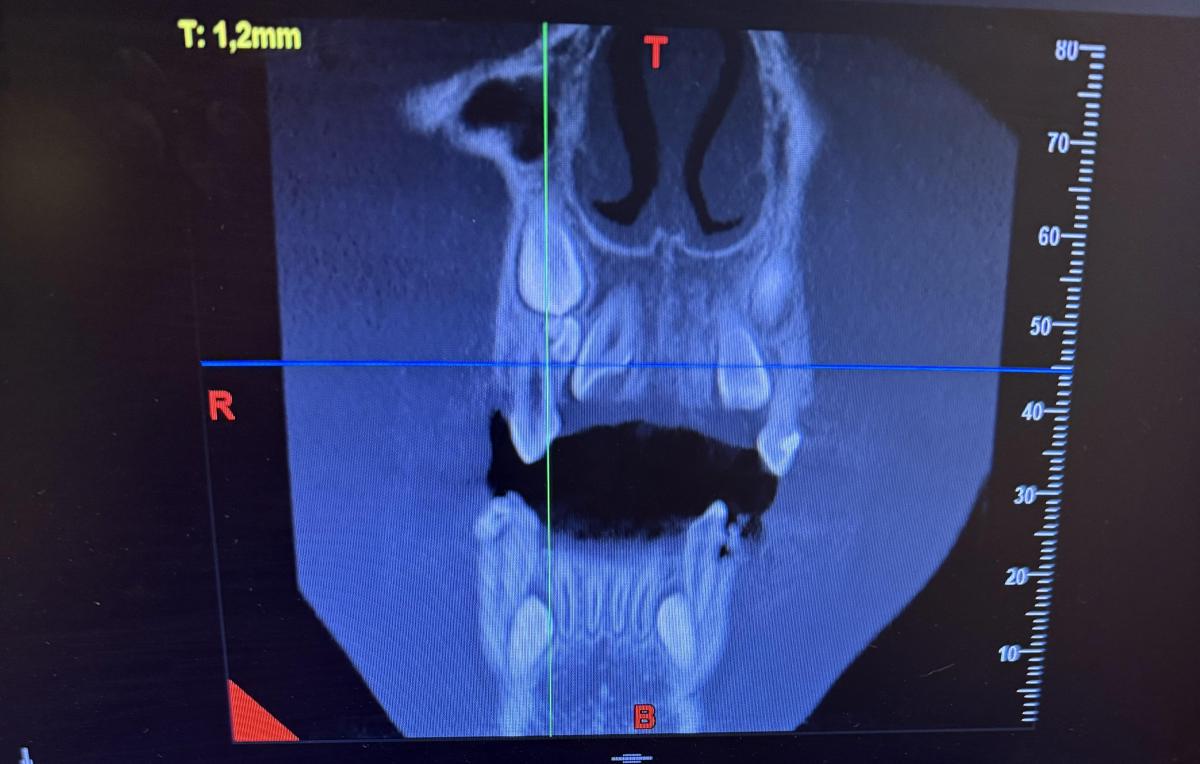

Здравствуйте, Ребекку 7 лет. Отсутствуют нижние зачатки 5 зубов. Верхний зачаток пятерки в недоразвитом состоянии и перевернут . Что с ним будет? Возможно ли что вырастет как надо? И основной вопрос- верхний клык (снимок прилагаю) между молочным и коренным обнаружено какое-то образование- это лишний зуб? Как его удалять? Вырывать молочный клык сейчас , далее удалять лишний и уже после ждать прорезывания постоянного? Или ждать пока молочный сам выпадет?